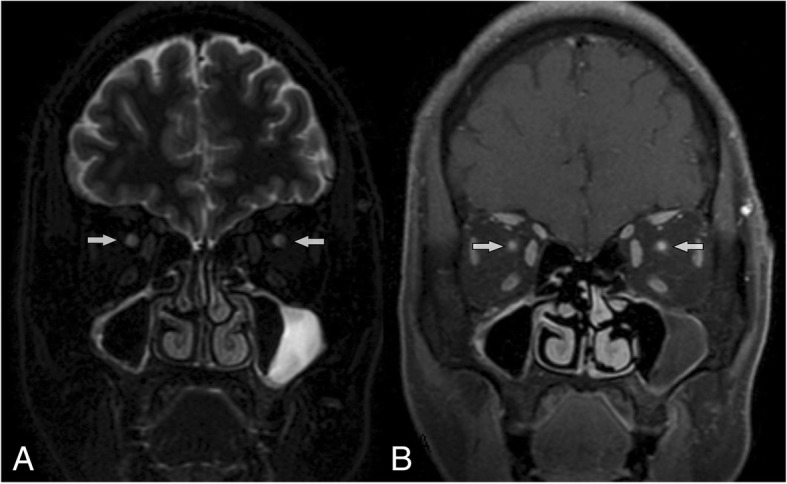

Physical examination showed that pupil light reflexes of 16 eyes were abnormal; isolated central scotoma was the characteristic of visual field defects; optic disk edema was found in 6/16 eyes, and normal optic disk in 10/16 eyes (Fig. 1); other neurologic examination results were normal. The results of auxiliary examination were shown in Table 2. Visual evoked potentials (VEPs) showed no fixed waveforms or poor waves in 15/16 eyes. All patients had poor eyesights as showed in Table 1, so they could not hold their eyes in fixed position. Abnormality of VEPs consisted in unelicitable evoked response in 13/16 eyes, and in latency prolongation in 2/16 eyes, which were combined with the decrease in amplitude. The values of prolonged latency were 141 ms and 143 ms separately. Optic nerve MRI with contrast demonstrated increased signals of bilateral optic nerves in the orbit and the canal parts, with enhancement (Fig. 2). Brain MRI showed non-specific demyelination in white mater or normal. Toxicological tests (urine and blood) were negative in all patients. The results of blood gas analysis and serum anti- AQP4-Ab tests were negative. All of the patients were transferred from several different primary hospitals in remote areas. Except one patient who had received hemodialysis, none was treated with ethanol, fomepizole, hemodialysis or methylprednisolone before being transferred. After treatments of large dosage of methylprednisolone combined with B vitamins in our department, the visual function of 5/8 patients got improved in different degree, but not satisfactorily, as shown in Table 3.

Fig. 2.

Coronal optic nerve MRI for patient 8. a sequence (T2-weighted imaging) showing hypersingnals in both optic nerves. b sequence (T1-weighted imaging with contrast and fat suppression) showing enhancement of both optic nerves

These patients in our reports showed different clinical characteristics from ingestion poisoning: (1) Severe visual loss was the main symptom, and might be a chronic poisoning course. As well known, methanol intoxication can cause severe visual dysfunction, especially irreversible bilateral blindness [1]. In current observation, bad visual function was still the outstanding manifestation. But 3 patients complained of constant slight blurred vision in one or both eyes before the acute visual loss, hinting the possibility that optic nerves had been partly injured since several months, which accorded with the characteristics of chronic intoxication. Moreover, the orbit MRI scans provided powerful evidence for ONs damage. Visual evoked potential demonstrated no potential or poor wave forms, which also suggested that the optic nerve damage was serious and bad prognosis. The selective optic nerve toxicity of methanol is striking and quite likely occurs because of a direct effect of the formic acid (metabolite of methanol in the body), which is thought to cause interruption of mitochondrial function in optic nerve, resulting in optic injury and loss of vision [10, 11], which is consistent with studies that showed high cytochrome oxidase activity in human optic nerve [12]. (2) The systemic symptoms were transient and self-limiting, while blood gas analysis was normal, and no distinctive abnormal focus or bleeding were found in basal ganglia regions on brain MRI images. Systemic effects are mainly due to metabolic acidosis resulting from accumulation of formic acid. In contrast to the cases of Korea [6], these clinical features were thought to be related to lower volume of inhaled methanol in a short period and lower concentration accumulated in body. In addition, the short half-life period of methanol and the delayed consulting time to our hospital contributed to these negative results of laboratory tests. However, this kind of lower poisoning still lead to disastrous visual impairment. It is well-documented that the level of toxicity, which does not correlate with the serum methanol level and hence, is not considered a good indicator of prognosis [13]. (3) Optic nerve MRI with contrast showed abnormal signals in optic nerve. To our knowledge, orbital MRI scan is rarely taken to observe the optic nerves in patients with methanol poisoning. Optic nerve and basal ganglia are the tissues most at risk from methanol intoxication for metabolic or apoptotic sensitivity to methanol metabolites. The typical manifestation on brain MRI scans in patients with ingestion poisoning was hemorrhagic or non-hemorrhagic necrosis in the bilateral putamen, occasionally in frontal and insular cortices and subcortices [14, 15]. But manifestation on orbital MRI scan for optic nerve in these patients is rarely reported. In our cases, increased signals of bilateral ONs in the orbit and the canal parts with enhancement were the common features (Fig. 2). All these data confirmed that the retrolaminar regions of the optic nerve were vulnerable to damage in methanol poisoning. However, these findings do not fully represent the characteristics of injured optic nerve in methanol poisoning, for most cases of methanol poisoning are caused by oral ingestion, not by inhalation.